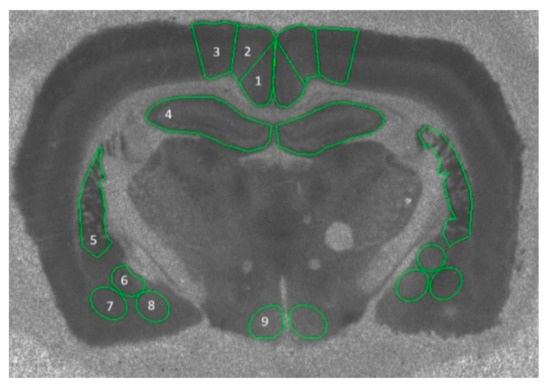

- Paxinos, G.; Watson, C. The Rat Brain in Stereotaxic Coordinates; Elsevier: Amsterdam, The Netherlands, 2006. [Google Scholar]

2.4. Autoradiography